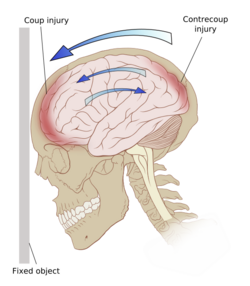

Ricochet of the brain within the skull may account for the coup-contrecoup phenomenon.[66]

Damage may occur directly under the site of impact, or it may occur on the side opposite the impact (coup and contrecoup injury, respectively).[66] When a moving object impacts the stationary head, coup injuries are typical,[68] while contrecoup injuries are usually produced when the moving head strikes a stationary object.[69]